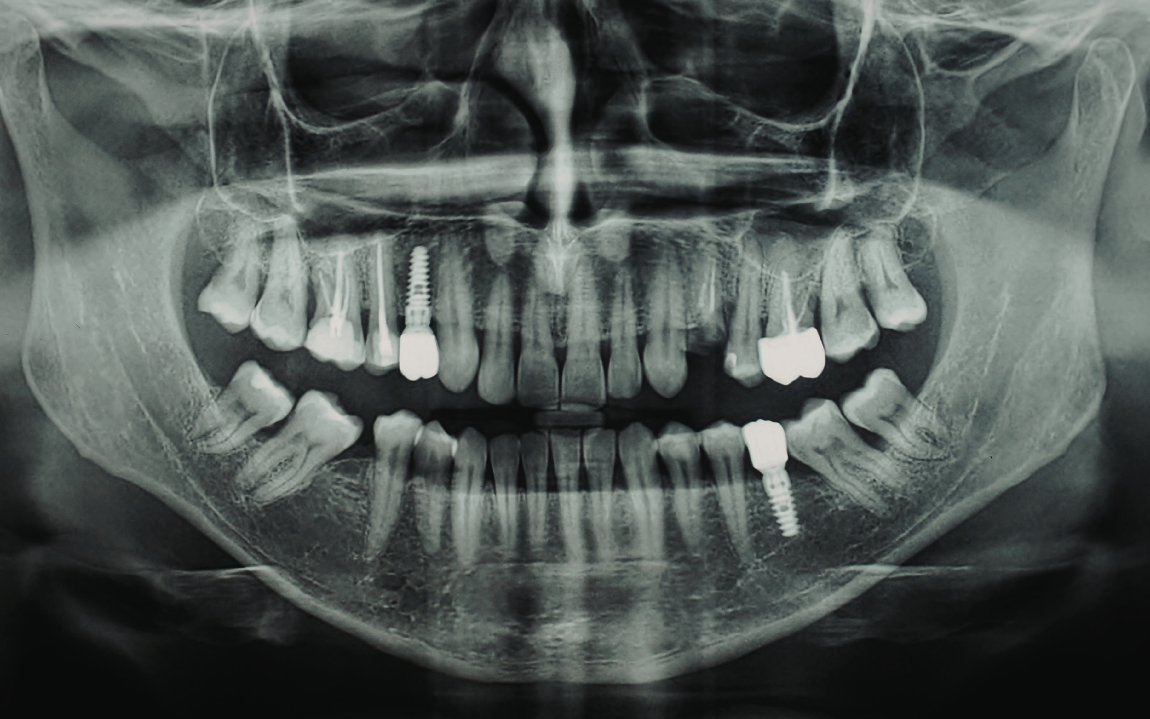

Un implante dental tiene dos componentes principales:

- El implante (tornillo de titanio)

- La corona (el diente visible)

Duración promedio:

- Implante: 20 años a toda la vida

- Corona: 10 a 15 años (puede requerir cambio por desgaste)